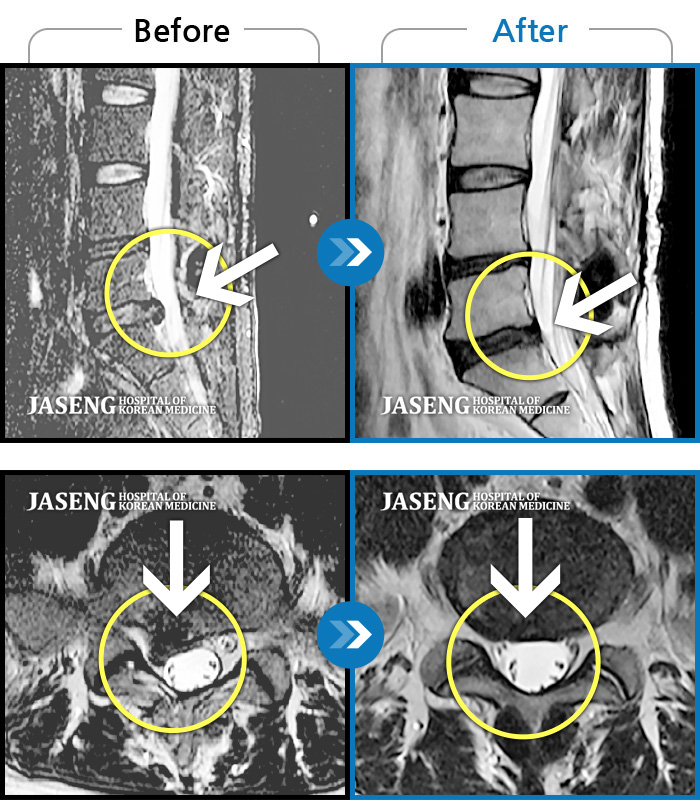

Before

After

환자에게 사전 동의를 받아 동일 조건에서 촬영되었습니다.

개인에 따라 치료 후 부작용이 발생할 수 있으니 의료진과 상담 후 치료를 진행하시기 바랍니다.

허리통증, 왼쪽 다리 저림 및 통증